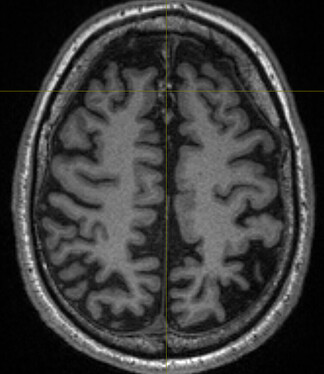

Upon further inspection, I noticed a midline “something” in the anatomical scan (below, anomaly marked by crosshair) extending several slices: